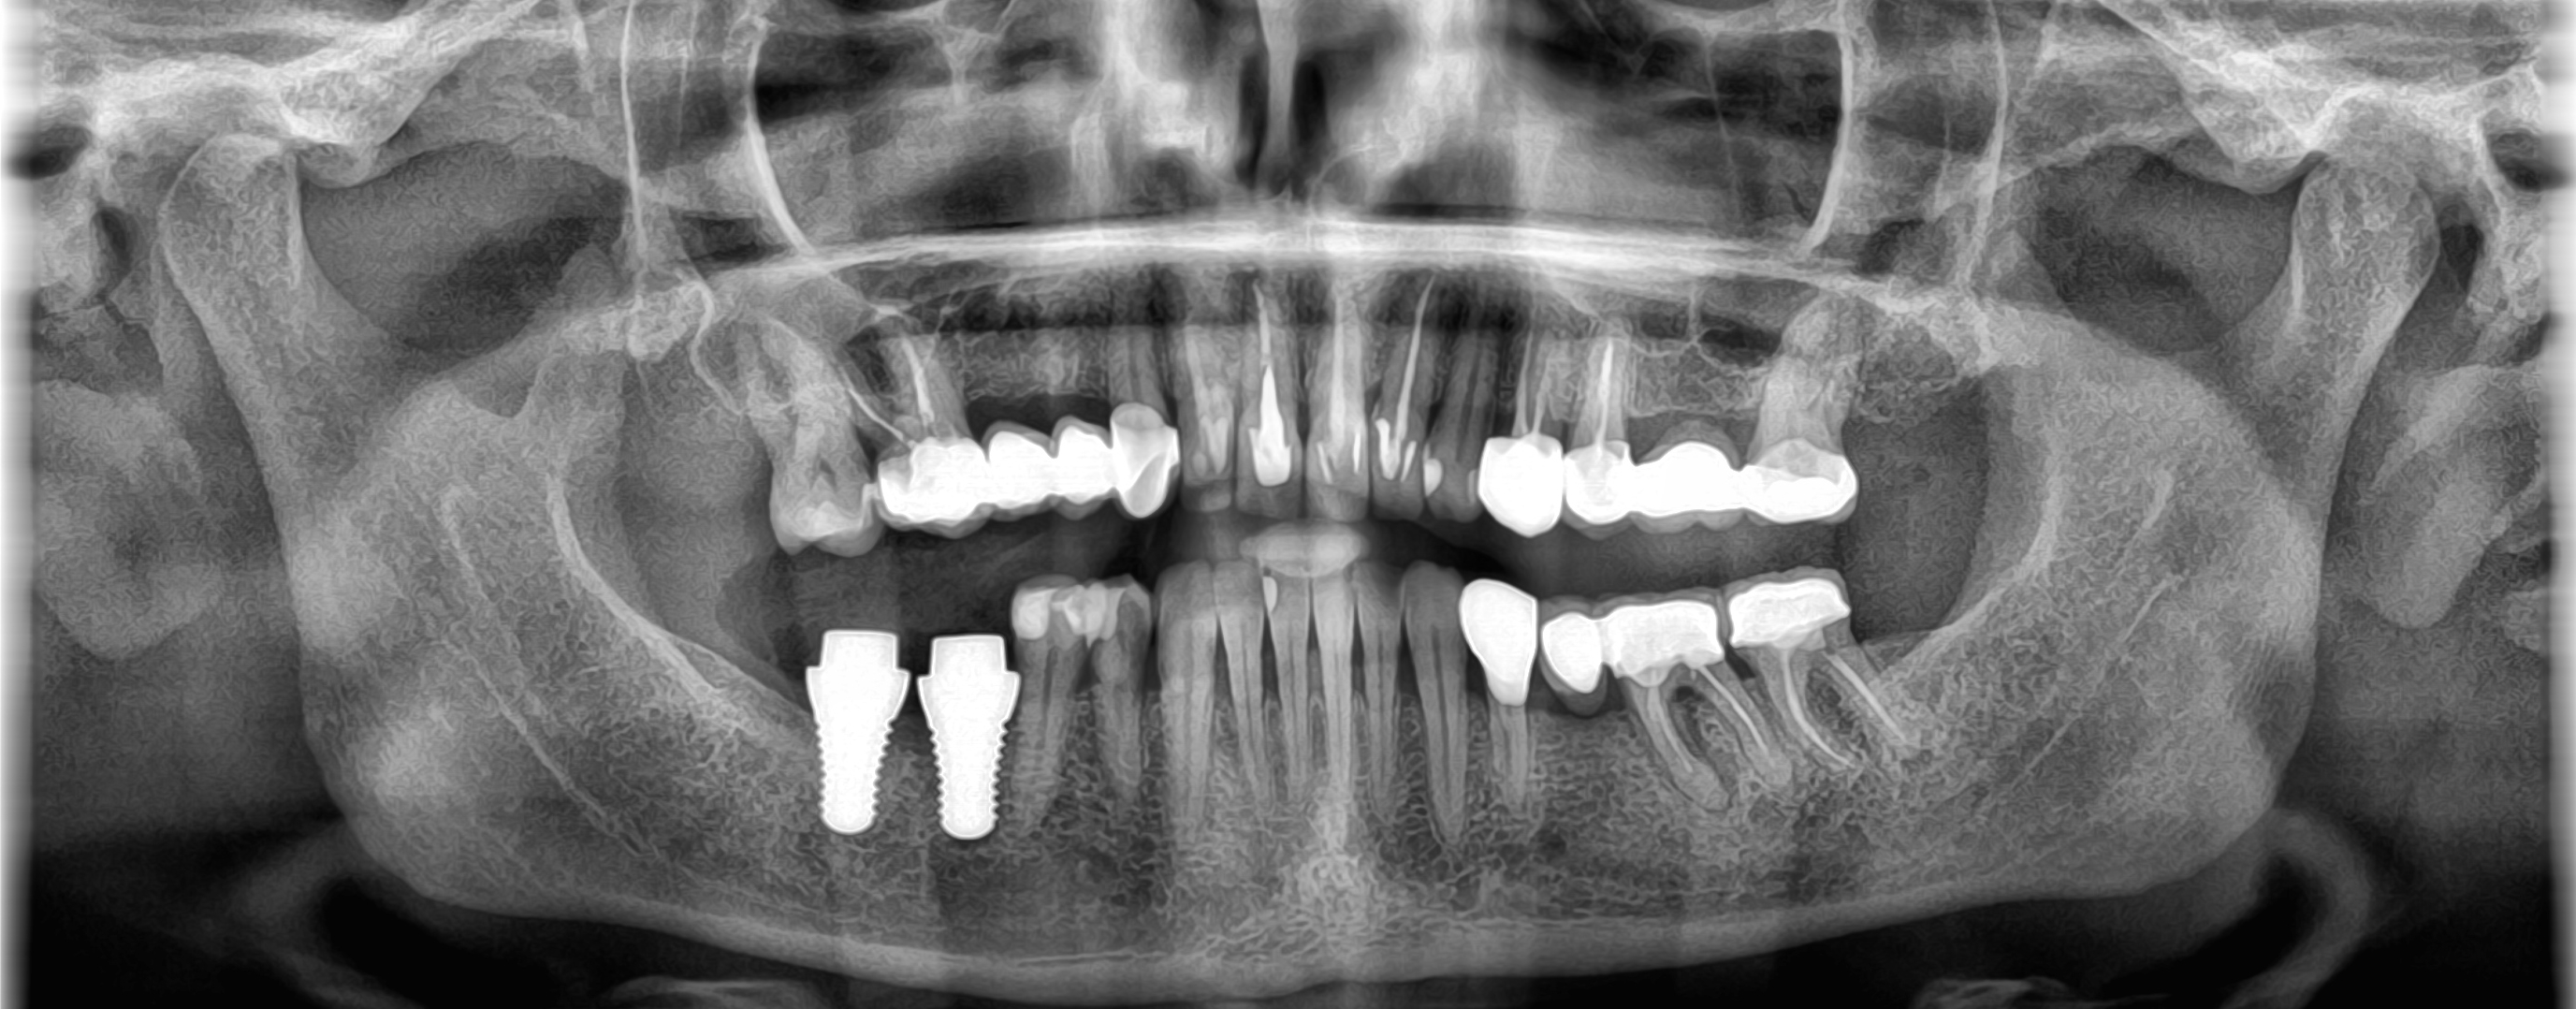

A dental implant has three main parts:

The Crown (or Prosthetic Tooth) – A custom-made tooth that matches your natural teeth in shape and colour.

The Abutment – A connector that attaches to the implant and supports the restoration.

The Implant Post – A small titanium or ceramic fixture that is placed into the jawbone, acting as an artificial root.

Over time, the implant integrates with your jawbone through a process called osseointegration, creating a strong, stable foundation.